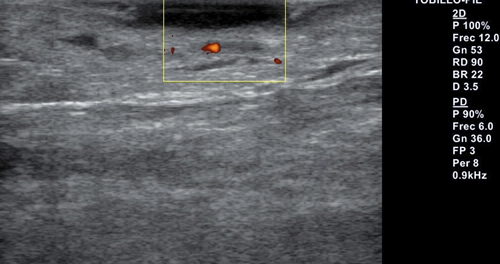

Se realiza exploración ecográfica vascular empleando para ello un equipo Alpinion E-cube 7 con una sonda lineal de 3-12 mHz, con una frecuencia de 12 mHz en la que destaca insuficiencia venosa y onda trifásica en arterias pedia y tibial posterior. Se realiza ecografía transulcerosa (Figura 2) mostrando área anecoica con punteado hiperecoico en su interior y con leve refuerzo acústico posterior, que afecta a la totalidad de la epidermis y penetra en dermis. Lesión bien delimitada, con ausencia de doppler en el interior de esta (Figura 3). Presenta una extensión ecográfica de 14 x 3.4 mm.

Figura 2. Ecografía transulcerosa en la que se observa la imagen anecoica con el punteado hiperecóico.